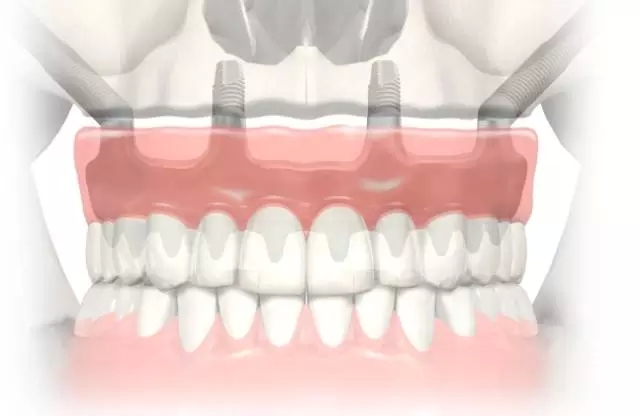

考古研究發(fā)現(xiàn),古埃及宮庭婦女就有采用骨內(nèi)種植動物牙和象牙雕刻的人造牙的記載,出土的人類頜骨化石中還發(fā)現(xiàn)鑲有寶石或黃金雕成牙體形狀的植入物,它是牙種植體的原始雛形,最早可以追溯到公元前6000年。 中國有記載的種牙歷史比較遲 約800多年前 陸游:“近聞有醫(yī)以補(bǔ)墜齒為業(yè)者。” 800多年前,我國宋代樓鑰所著的《玫瑰集》中,也記載著了種牙。 宋代的大文豪陸游,不僅是一位豪放詩人,也是一位醫(yī)學(xué)愛好者。在陸游的《歲晚幽興》中說:“卜冢治棺輸我快,染須種牙笑人癡。”更可貴的是,他還在詩后面加了自注:“近聞有醫(yī)以補(bǔ)墜齒為業(yè)者。” 為了口腔健康,世界各國的人們想盡了辦法! 公元前4世紀(jì),古希臘人就用人牙、動物牙、黃金和木材料來做人的假牙。 意大利西北部的伊特拉斯坎人在公元前700年就開始制作假牙,然后用金制箍條固定在鑲牙者口中。 在18世紀(jì)曾有從事“獵牙”者。1815年的滑鐵盧戰(zhàn)役留下的巨大牙齒資源,那一仗,拿破侖損失了3萬將士,英普等聯(lián)軍損失了2.3萬將士,這幾萬套“滑鐵盧牙齒”整整服務(wù)了歐美一代鑲假牙的人。 為了一顆好牙,人類的道德底線被擊穿了。 曙光與低谷 30年代至60年代的徘徊不前 1947年,M. formiggini以鉭絲錐形體植入口腔頜骨 1947年,M. formiggini以鉭絲錐形體植入口腔頜骨,成功地完成了義齒修復(fù),他被譽(yù)為口腔種植學(xué)的奠基人,口腔種植技術(shù)似乎看到了曙光。 但由于在五六十年代種植義齒的臨床應(yīng)用過分超前于基礎(chǔ)研究,造成種植高失敗率。1973年,國際衛(wèi)生研究所和美國牙醫(yī)學(xué)會的牙科材料委員會經(jīng)調(diào)查,對種植義齒持否定態(tài)度,牙種植由此一度跌入低谷。 終于找到開啟金色大門的鑰匙 1952-1982年,現(xiàn)代口腔種植學(xué)開啟 1952年,Br?nemark發(fā)現(xiàn)骨和純鈦能發(fā)生結(jié)合, 基礎(chǔ)研究的突破帶來了質(zhì)的飛躍 20世紀(jì)60年代,Br?nemark教授首次提出口腔植入體使用高純度的鈦金屬替代以往的黃金等貴金屬成為新的植入材料。他在動物實(shí)驗(yàn)中發(fā)現(xiàn),骨組織與植入的純鈦種植體結(jié)合得異常牢固,形成了一個完美的整體。 基于此項(xiàng)研究結(jié)果,Br?nemark教授創(chuàng)立了全新的骨結(jié)合理論:即人體活的骨組織與鈦種植體之間發(fā)生牢固、持久而直接的結(jié)合。該理論的確立在種植體領(lǐng)域掀起了革命性的變化。 在有記載的7000多年口腔種植歷史中,人類一直站在這扇厚重的金色大門前,束手無策。Br?nemark教授重于找到了開啟金色大門的鑰匙,人類正式步入現(xiàn)代口腔種植學(xué)的殿堂。 在這30年中 Br?nemark教授和他的團(tuán)隊(duì) 克服了無數(shù)的困難與質(zhì)疑 由于厚積了幾千年的失敗經(jīng)驗(yàn),物理學(xué)家和牙醫(yī)們思想已經(jīng)被牢牢固化。他們認(rèn)為非生物材料不可能融入活的生物組織——最初的炎癥和最終的排異是不可避免的,這個過程也會給病人帶來極大的痛苦。 Br?nemark教授的發(fā)現(xiàn)有悖“傳統(tǒng)智慧”,因此,即使在1965年Br?nemark教授為G?sta Larsson先生成功的進(jìn)行了鈦種植體種入,前方的路途依然漫長而坎坷。 現(xiàn)代口腔種植學(xué)的起源一方面來自骨結(jié)合理論的確立,另一方面還源于Br?nemark教授建立起的現(xiàn)代口腔種植標(biāo)準(zhǔn)化操作流程,他所著的《OSSEOINTEGRATED IMPLANTS》一書是現(xiàn)代口腔種植學(xué)的第一座里程碑。 在1982年多倫多召開的牙科種植大會上,Br?nemark教授向與會者展示了其團(tuán)隊(duì)在齒科種植體領(lǐng)域15年的工作成績。從骨結(jié)合理論的發(fā)現(xiàn)與應(yīng)用,到大量的、全新整理的科學(xué)實(shí)驗(yàn)數(shù)據(jù)以及世界第一例成功種植牙臨床病例,終于獲得了與會者廣泛的關(guān)注和認(rèn)可。 1982年多倫多召開的牙科種植大會 向Br?nemark教授和他的團(tuán)隊(duì)致敬! 在金色大道上高歌前行 Nobel Biocare 時代來了 1978年,諾貝爾工業(yè)集團(tuán)與Br?nemark教授開始合作,1981年Nobelpharma AB公司成立,1996年,公司更名為今天的Nobel Biocare公司。 一 Br?nemark System® Nobel Biocare經(jīng)久耐用的Br?nemark System®,G?sta Larsson先生使用了該系統(tǒng),運(yùn)行40年依舊穩(wěn)固如新。 二 NobelReplace® Tapered Replace Select™ Tapered NobelReplace® Tapered(諾保易配錐形)及Replace Select™ Tapered(易配精選錐形)模仿自然牙根的形狀,該設(shè)計(jì)在所有負(fù)重方案,包括即刻行使功能中,都能取得極高初始穩(wěn)定性。 更新、更領(lǐng)先的系統(tǒng) NobelReplace® CC (Conical Connection) NobelReplace® CC (Conical Connection)結(jié)合獨(dú)創(chuàng)的錐形種植體主體和緊密密封的錐形連接體,為您和您的患者提供了一種適用于所有適應(yīng)證的美齒解決方案。種植體主體可模擬自然牙根的形狀,旨在實(shí)現(xiàn)各種負(fù)重治療方案(包括 Immediate Function-即刻行使功能)的較高初期穩(wěn)定性。 NobelReplace® CC (Conical Connection)2011年全球上市(2015年中國上市)。 三 NobelActive® NobelActive®是具有劃時代意義的種植體。其體部及螺紋設(shè)計(jì)可以在植入時使進(jìn)行骨擠壓,即使在骨質(zhì)受損的情況下,也可以獲得很高的初始穩(wěn)定性。這使之成為即刻種植的理想之選。另外,頂部帶鉆刃的反向切割槽,可以調(diào)整種植體方向,以獲得最佳修復(fù)方向。 NobelActive®2008年全球上市(2012年中國上市)。 四 NobelSpeedy®系統(tǒng) NobelSpeedy®系統(tǒng)即使在軟質(zhì)骨中使用也有很高的初始穩(wěn)定性,操作高效省時,同時具有卓越的多功能性和享受修復(fù)靈活性,特別是在快速骨形成的愈合時期保持很高的穩(wěn)定性,確保長期成功。 All-on-4®治療概念由帶有外六角的NobelSpeedy®種植體發(fā)展而來。 什么是 All-on-4® 概念? 開發(fā) All-on-4 臨床解決方案的目的在于最大限度地利用可利用骨量并支持即刻負(fù)重。 四顆種植體支撐全口無牙頜: 2顆前牙種植體,直的 2顆后牙種植體,傾斜的 全口樹脂牙橋進(jìn)行即刻、臨時、固定修復(fù)與負(fù)重。 All-on-4®是NobelBiocare的注冊商標(biāo)